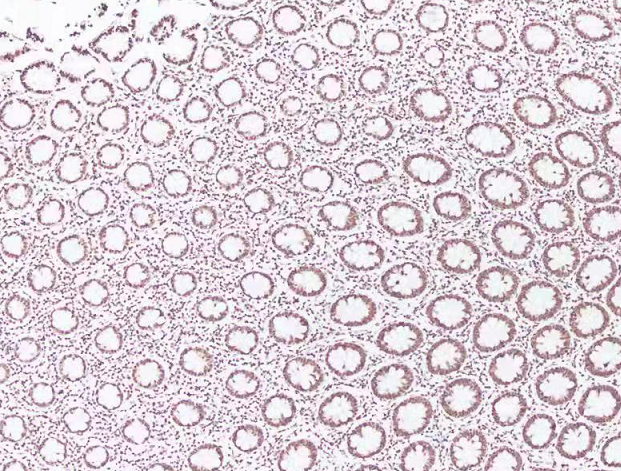

结肠H3    100倍